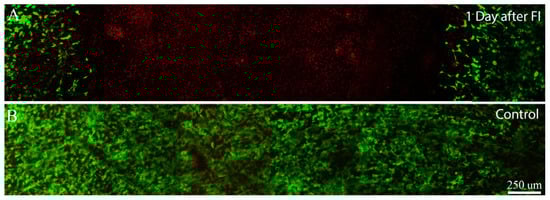

Error in Figure